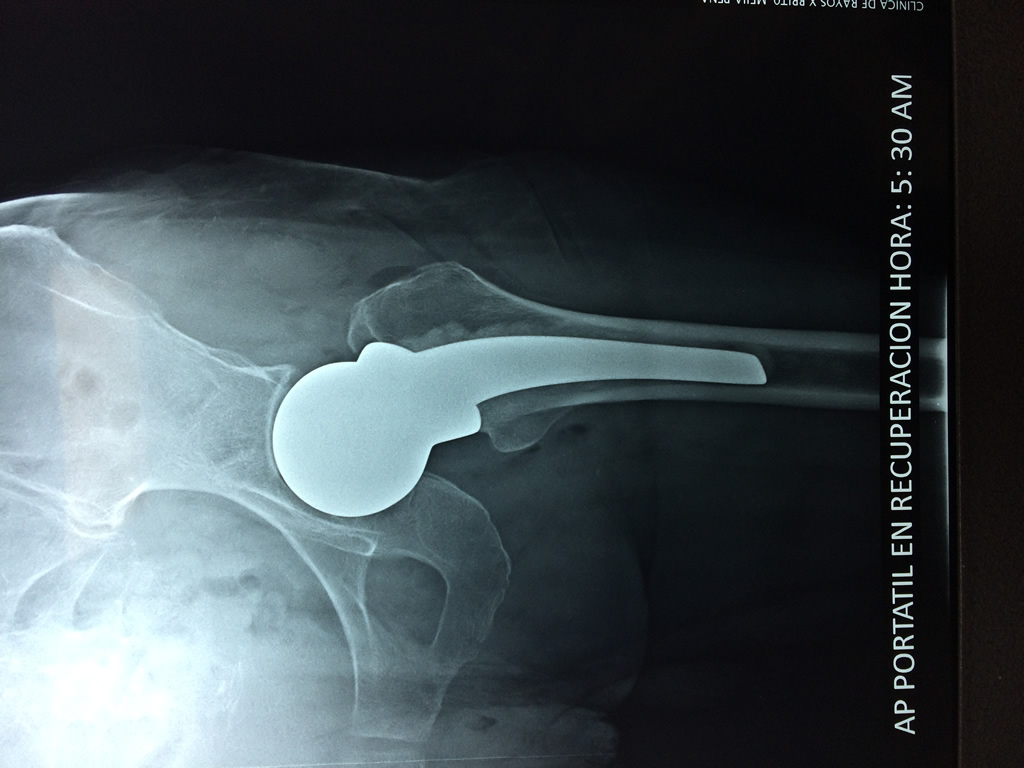

Fémur - Cadera

La cirugía de fractura de cadera se realiza para reparar una ruptura en la parte superior del hueso del muslo. Este hueso se denomina fémur.

Es parte de la articulación coxofemoral. Si una fractura de cadera no recibe tratamiento, es posible que deba permanecer en una silla o en la cama.